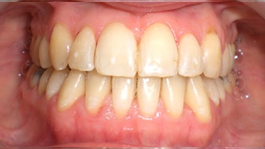

Présentation cas clinique :

Avant traitement

Après traitement